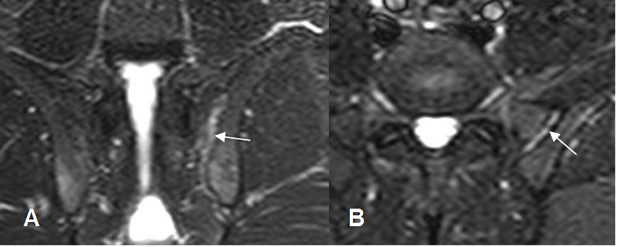

Fig 10 A. Sacroileitis.

A: RM coronal y B: RM axial en STIR. Signos de sacroileitis izquierda incipiente, con escaso líquido articular.

Fig 10 B. Sacroileitis.

A: RM axial en T2 y B: RM coronal en STIR. Zona hiperintensa, por inflamación del cartílago. (Flechas). Además hay imágenes hiperintensas en el sacro, por osteitis.